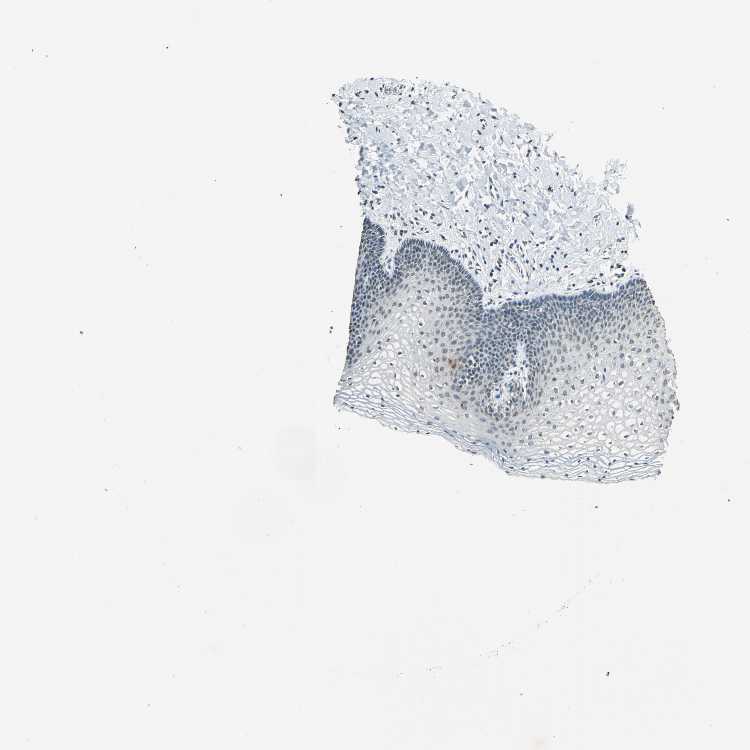

TISSUE PRIMARY DATA VAGINA Show tissue menu

VAGINA - Antibody stainingi

Antibody staining in the annotated cell types in the current human tissue is reported as not detected, low, medium, or high, based on conventional immunohistochemistry profiling in selected tissues. This score is based on the combination of the staining intensity and fraction of stained cells.

Each image is clickable and will lead to virtual microscopy that enables deeper exploration of all samples and also displays staining intensity scores, fraction scores and subcellular localization as well as patient and tissue information for each sample.

Antibody HPA015497Antibody CAB006319

Squamous epithelial cells MediumLow